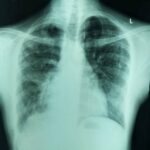

호흡은 우리가 아무 생각 없이 하는 일입니다. 하지만 일부 사람들에게는 만성 폐쇄성 폐질환(COPD) 및 천식과 같은 질환으로 인해 호흡이 정말 힘들어질 수 있습니다.

이 두 가지 호흡기 질환은 자유롭게 호흡하는 능력에 큰 영향을 미칠 수 있는 흔한 호흡기 질환입니다. 이 글에서는 만성 폐쇄성 폐질환과 천식의 원인과 증상, 그리고 가장 중요한 삶의 질 향상을 위한 관리 방법에 대해 자세히 알아보세요.

만성폐쇄성폐질환은 만성폐쇄성폐질환의 약자입니다. 기도가 막히고 폐 조직이 손상되어 숨쉬기가 어려워지는 폐 질환 그룹입니다.

COPD의 두 가지 주요 질환은 만성 기관지염과 폐기종입니다. 이 두 가지 질환은 시간이 지남에 따라 점차 악화되어 폐에 충분한 공기를 공급하는 것이 점점 더 어려워집니다.

COPD는 하루아침에 나타나지 않습니다. 서서히 진행되며, 증상을 노화의 일부로 치부할 수도 있습니다. 호흡곤란, 점액을 동반한 지속적인 기침, 쌕쌕거리는 숨소리, 가슴 답답함 등이 COPD의 일반적인 증상입니다.